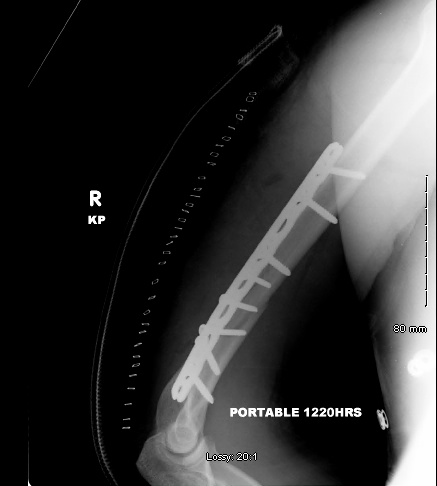

The patient underwent an open reduction and internal fixation of the fracture using a 4.5mm narrow non locking compression plate along with placement of inter-fragment lag screws (3 x 3.5 mm screws).

| AP view after surgery and plating using 4.5mm plate and 3 lag screws |

Lateral view after the placement of the plate |